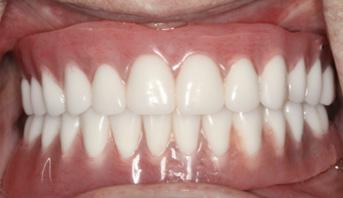

After three months of healing, the patient returned to the AEGD clinic to confirm osseointegration of implants and to begin the overdenture fabrication process. At the final impression appointment, signs of arthritis including knuckle enlargement were noted. Due to this finding, it was determined that changing the patient's final prosthesis from a Conus overdenture to a conventional overdenture was in the best interest of the patient, as the Conus would be too cumbersome for her. As seen in Figures 1 and 2, the outcome turned out very well and the patient was pleased with results and esthetics.

FIGURE 1

FIGURE 2